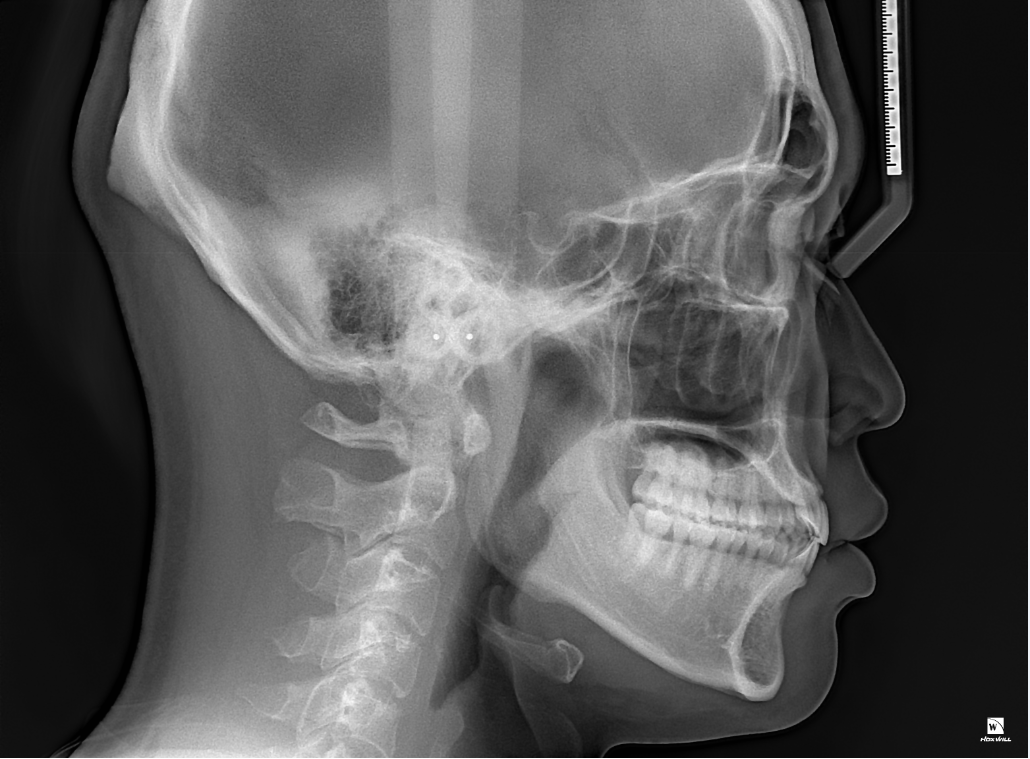

식사를 하거나 일상생활에서 교합을 하는데 큰 문제가 없다면 정상교합으로 판단합니다.

피개량이 적긴하지만 위에 치아가 아래 치아를 덮고 있다면 반대교합이나 절단교합이 아닌 정상교합의 범주에 있다고 판단을 하게 됩니다.